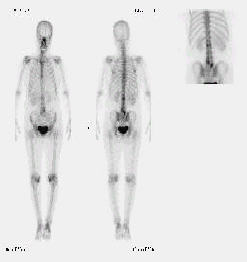

그 외 다른 장기로의 전이 유무 확인을 위해 흉부촬영, 골주사 검사 등을 시행하게 됩니다. 각각의 영상진단법의 특징은 아래와 같습니다.

○ 골주사

골전이가 의심될 때 전이 유무를 판단하기 위해 시행합니다.

그림 4. 다발성 척추전이가 있는 골주사사진